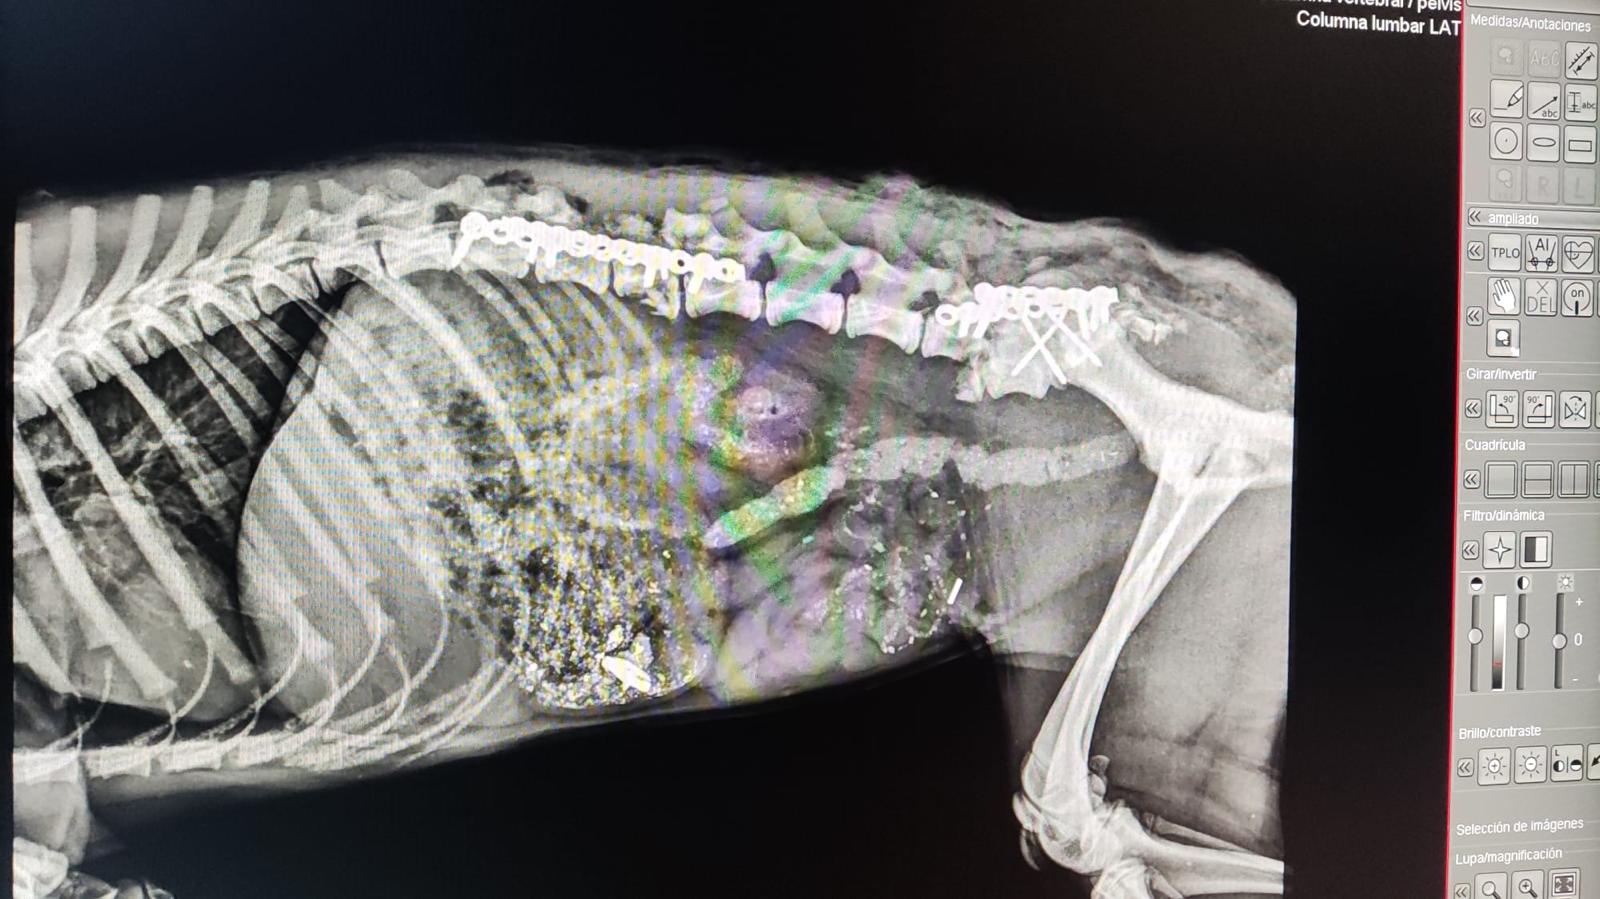

29.1.24: Leider sind die Resultate ernüchternd! Das Kleine hat vermutlich das Rückgrat gebrochen und da sind keine guten Prognosen…

Als Eva Chula in der Klinik besuchen wollte sah sie auf der Autobahn dieses kleine Wesen, das von einem Auto massiv erfasst worden war. Schnell war das ca 5,5 Monate alte Welpchen eingepackt und liegt nun in derselben Klinik wie Chula. Es muss einen massiven Schlag auf den Kopf bekommen haben und auch die Hinterbeine sind betroffen. Es muss geröntgt werden, noch wissen wir nicht, ob es überlebt…